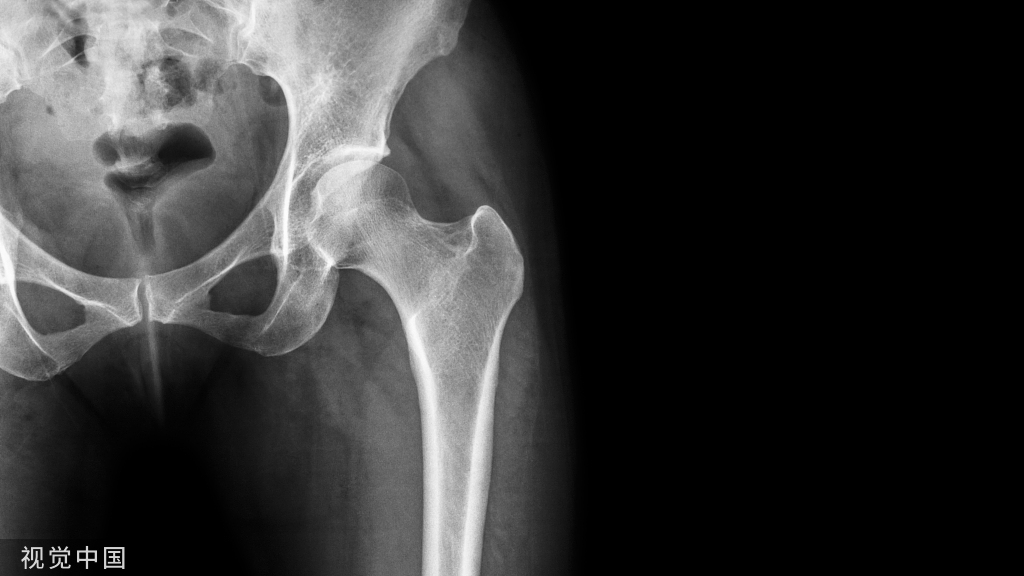

X 线平片上表现为伴有清晰薄层硬化缘的环形(囊状)透亮区,CT 上表现为圆形 或类圆形的皮质下局灶性骨质缺损,周围见薄层硬化带环绕 边缘锐利,部分较大病灶在病灶层面或上下相邻 、层面上前方显示皮质与病灶相通的局部裂隙样缺损病灶,最大径线通常小于 10 mm;MRI 示病灶在 T1WI 上呈低信号,在 T2WI 上呈均匀或不均匀高信号。